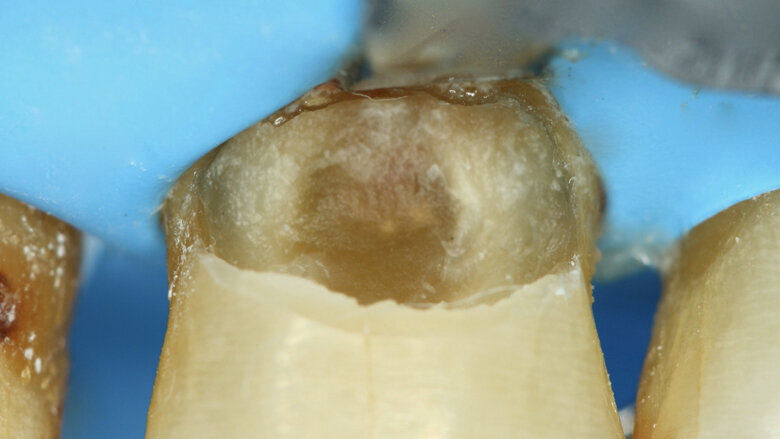

Figura 1. Lesiones de caries cavitadas en dentina activa (ICDAS 5) en dientes 11 y 21 en paciente másculino (Caso 1).

Paciente masculino de 65 años de edad se presenta al consultorio con lesiones de caries cavitadas en dentina activa (ICDAS 5) en dientes 11 y 21 (Figura 1). La lesión de la pieza 21 es extensa, mediante examen radiográfico y pruebas de vitalidad se diagnostica ausencia de compromiso pulpar. Como la lesión se extiende infra-gingivalmente, se opta por colocar dos hilos retractores 000 y 00 (Ultrapack, Ultradent, EE UU) y aislamiento absoluto con hilo dental tipo teflón y un clamp para anteriores (Figuras 2 y 3). Se inicia el procedimiento de remoción químico-mecánica utilizando un agente enzimático (Brix3000, Brix Medical Science, Argentina) durante 2 minutos (Figura 4). Utilizando curetas (Maillefer, EE UU) se elimina la dentina infectada (Figura 5) y el esmalte sin soporte dentinario (Figura 6) es eliminado con una fresa multilaminada (Figura 7) para mejorar el mimetismo y la adhesión al esmalte. Se complementa la instrumentación mecánica en el límite amelo-dentinario (Figuras 8 y 9).